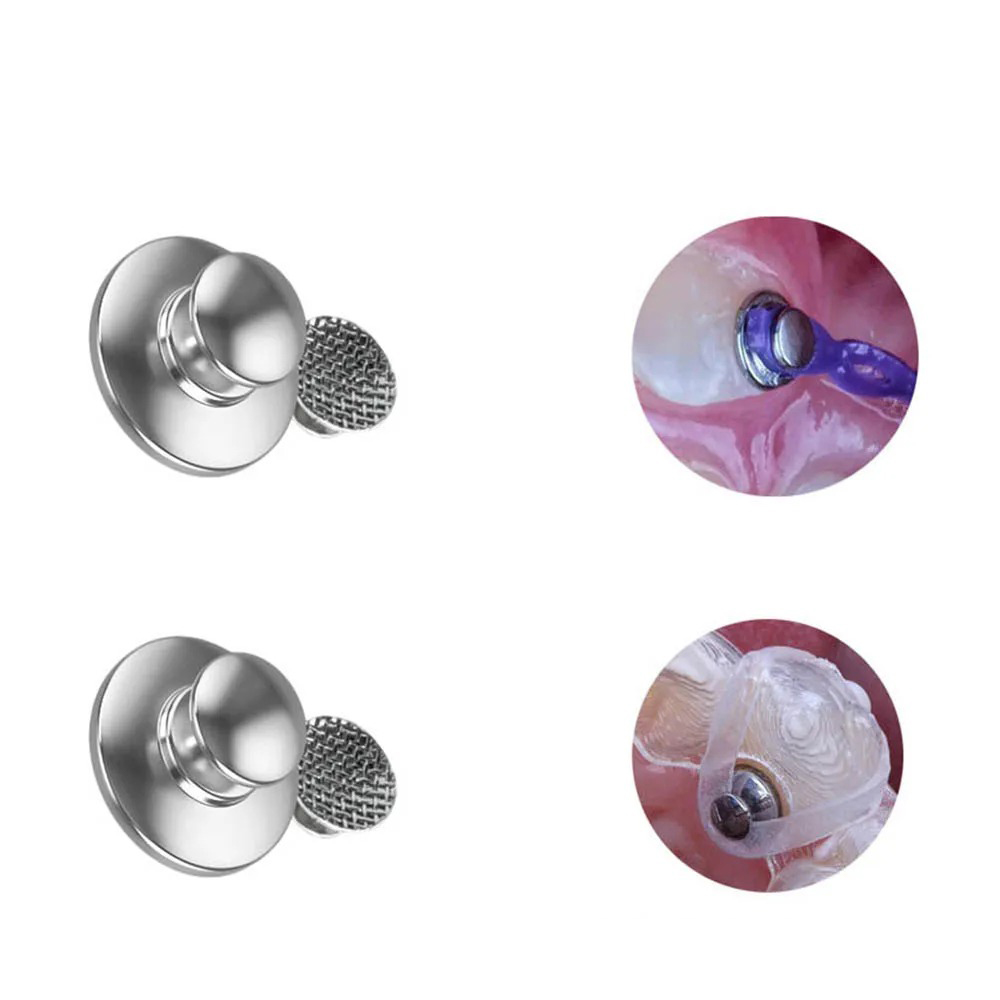

- Bondable Buttons with a Round Base: Bondable Buttons with a round base provide a stable attachment point for orthodontic accessories. The round shape ensures secure bonding to the tooth's surface.

- Lingual Perforated Bondable Button: Lingual Perforated Buttons feature small perforations or holes, allowing for the passage of elastics or archwires. This design provides flexibility in adjusting forces.

- Preparation: The tooth's surface is cleaned and etched to create a suitable bonding surface. The Bondable Button is then placed on the tooth.

- Bonding: Orthodontic adhesive is used to secure the Bondable Button to the tooth's surface. Careful placement and bonding are essential for stability.